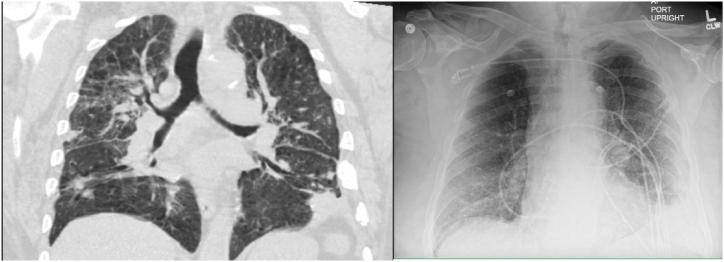

A 67-year-old immunocompetent male with COPD on supplemental oxygen presented with shortness of breath and was initially treated for bronchitis exacerbation with initial suspicion of bacterial pneumonia. He was later found to have EBV pneumonia diagnosed via positive EBV on bronchoalveolar lavage PCR. Severe lung involvement has been rarely reported in context of acute EBV infection. Treatment for this entity has not yet been established, with few reports of acyclovir and steroid use. This report describes the presentation, diagnosis, and treatment of acute EBV pneumonia.

一名67岁免疫功能正常的男性,患有慢性阻塞性肺疾病(COPD)且需吸氧,因呼吸急促就诊,最初因怀疑细菌性肺炎而按支气管炎加重进行治疗。后来经支气管肺泡灌洗PCR检测EBV呈阳性,确诊为EBV肺炎。在急性EBV感染的情况下,严重肺部受累的情况鲜有报道。针对该病症的治疗方法尚未确定,仅有少量使用阿昔洛韦和类固醇的报告。本报告描述了急性EBV肺炎的临床表现、诊断和治疗。